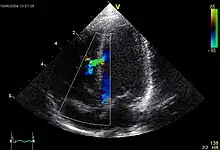

A VSD can be detected by cardiac auscultation. Classically, a VSD causes a pathognomonic holo- or pansystolic murmur. Auscultation is generally considered sufficient for detecting a significant VSD. The murmur depends on the abnormal flow of blood from the left ventricle, through the VSD, to the right ventricle. If there is not much difference in pressure between the left and right ventricles, then the flow of blood through the VSD will not be very great and the VSD may be silent. This situation occurs a) in the fetus (when the right and left ventricular pressures are essentially equal), b) for a short time after birth (before the right ventricular pressure has decreased), and c) as a late complication of unrepaired VSD. Confirmation of cardiac auscultation can be obtained by non-invasive cardiac ultrasound (echocardiography). To more accurately measure ventricular pressures, cardiac catheterization, can be performed.

Intraoperative transesophageal echocardiography is used to confirm secure closure of the VSD, normal function of the aortic and tricuspid valves, good ventricular function, and the elimination of all air from the left side of the heart.